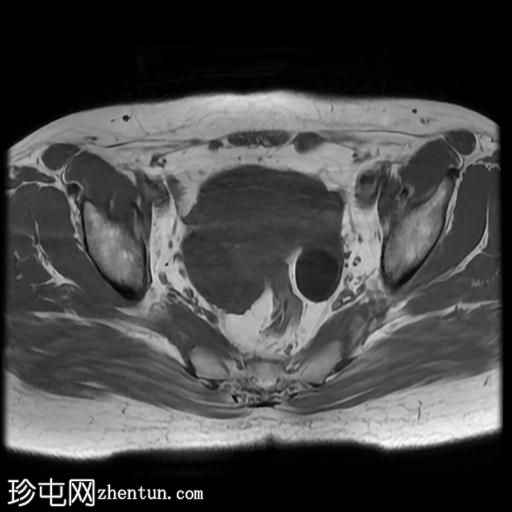

轴位

T1加权像

右侧输卵管呈管状囊性扩张,直径达30 mm,提示输卵管积水,呈均匀液体信号,无实性成分。

左侧输卵管亦有轻度扩张,直径26 mm,符合输卵管积水表现。

右侧卵巢可见一单纯性卵巢囊肿,大小约35 x 40 mm,呈正常液体等效信号。

宫内节育器位置正常。

MRI 检查结果显示双侧输卵管积水和右侧卵巢单纯性囊肿。总体而言,所有附件和盆腔检查结果均显示良性 MRI 特征(O-RADS 2 类),无恶性肿瘤迹象。